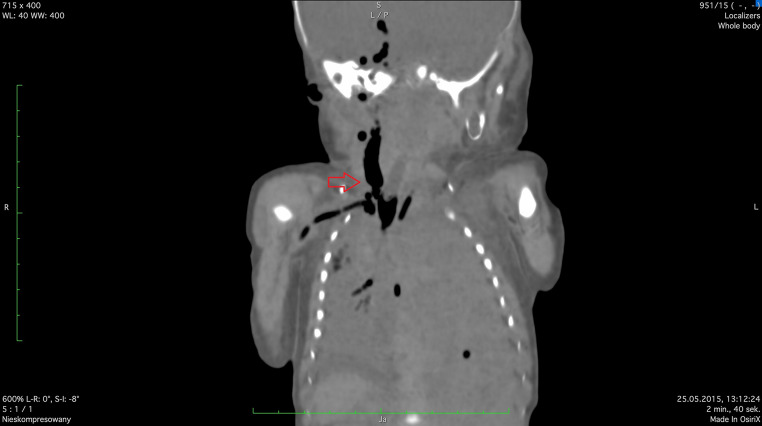

Congenital diaphragmatic hernia is associated with high risk of neonatal death. It is observed in about 1 in 3,000 live births. Fetoscopic tracheal occlusion procedure is a therapeutic option with survival rate 46.4%. Our aim was analysis of the suitability of postmortem computed tomography in the case of neonatal death occurred after fetoscopic endotracheal occlusion performed due to the severe isolated left-sided congenital diaphragmatic hernia. Postmortem computed tomography can be helpful in such cases because it allows for an objective assessment of whether the procedures used after the birth of the newborn enabled effective lung ventilation. Our case was the first use of postmortem computed tomography in neonatal death after fetoscopic endotracheal occlusion worldwide.

Abstract Image